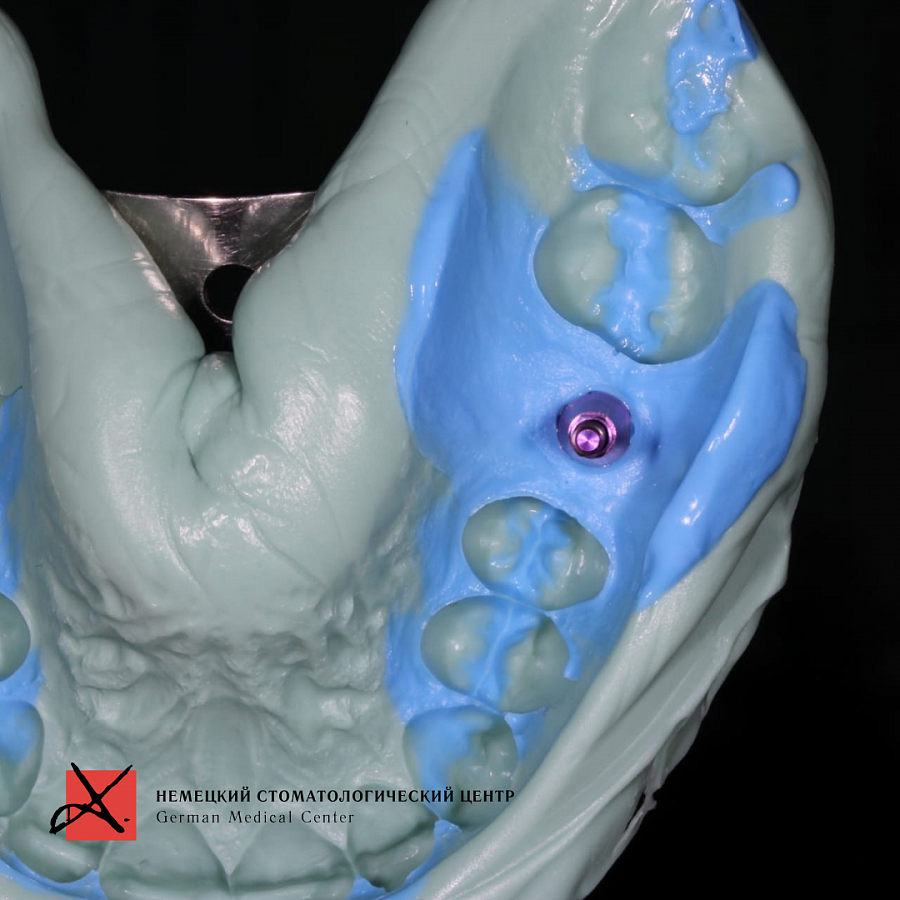

На рентгеновском снимке виден костный дефект после удаления, а также перелом вестибулярной стенки.Этапы лечения

Провели костную пластику с последующей имплантацией. Материал для пластики - Geistlich Bio - Oss ( Био Осс ) - натуральный костнозамещающий материал, покрытый мембраной. Через 6 месяцев провели имплантацию и далее протезирование.